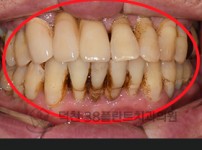

치료전후